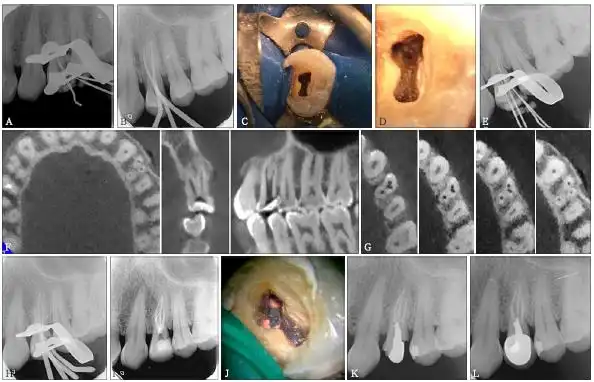

上颌第一磨牙远颊双根管1例

右上颌第一磨牙rct治疗一例赏析第三届萨尼蓝色梦想杯根管大赛

罕见上颌第一恒磨牙6根管的病例报告暨plex锉的根管治疗之路济南博士

上颌第一前磨牙4根管1例

上颌第一磨牙根管治疗流程

上颌前磨牙s形弯曲根管一例